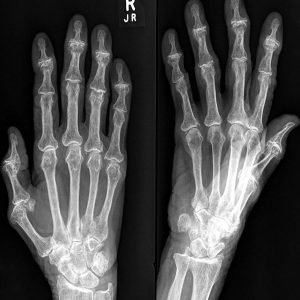

Is Your Arthritis Active?

Calculate your arthritis score and share it with your rheumatology team.